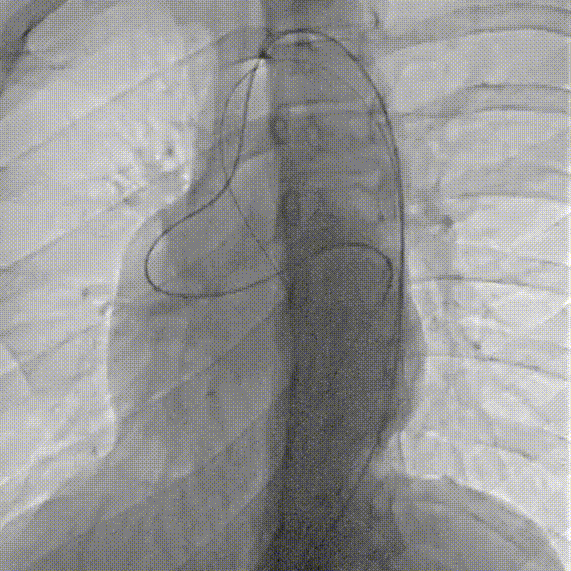

主动脉根部造影显示粗大右冠并分流至左心室显影。

经右侧股动脉在5F单弯导管引导下将260cm泥鳅导丝送至右冠状动脉开口,导丝序贯通过瘘口-左心室-主动脉瓣-升主动脉,

经左侧股动脉在MPA导管引导下将抓捕器放置于无名动脉,抓捕泥鳅导丝,建立轨道